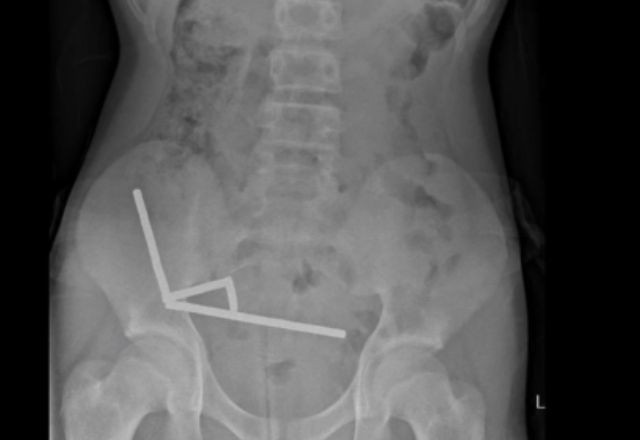

O garoto ingeriu entre 80 e 100 ímãs de neodímio, um material extremamente magnético – cerca de uma semana antes. Cada um deles media cinco milímetros por dois milímetros, segundo o relatório da revista científica. Os objetos foram comprados em um site internacional, segundo o menino.

Ele foi internado após quatro dias de dores abdominais e exames de imagem mostraram correntes de ímãs aderidas entre diferentes partes do intestino, unidas pela força magnética. O contato prolongado causou necrose por pressão e risco de perfuração intestinal.

Durante a cirurgia, os médicos encontraram quatro áreas necrosadas e precisaram remover parte do intestino para retirar todos os ímãs. Após oito dias de internação e tratamento de complicações leves, o paciente recebeu alta. O hospital onde o procedimento foi realizado não foi divulgado.